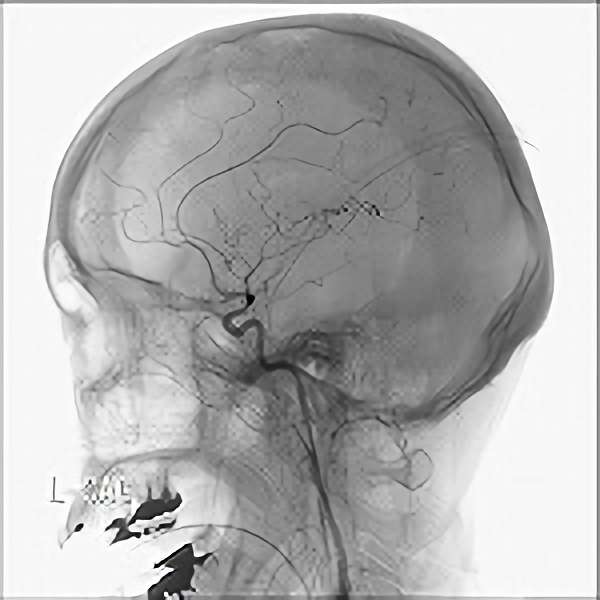

脳血管撮影

手術前

手術後

手術中

モニタリング

手術写真

手術の結果